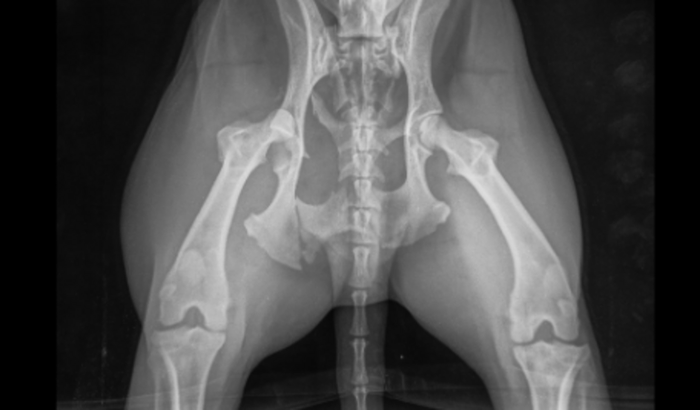

Resgatei esse cachorrinho de rua que foi atropelado hoje 04/08/2022 na beira-mar, precisamos de ajuda para o curtos veterinário e pós. ele está como muita escoriações, fêmur quebrado e bacia não consegue encaixar com o osso do fêmur, será necessária cirurgia. Por favor nos ajude!